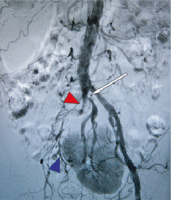

Abbildung 3: Interventionsergebnis in der DSA-Beckenübersicht nach Stentimplantation. Die weißen Pfeile markieren die Stentstrecke, erhaltene Perfusion der Kuchenniere (roter Pfeil).